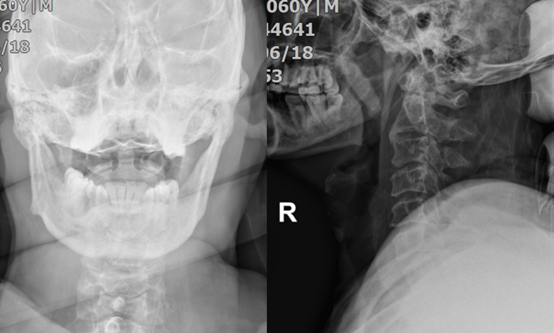

主要的辅助检查(图1-3):颈椎正侧位+张口位:未见明显颈椎骨折及脱位。颈椎MRI:1、颈脊髓损伤;2、C3/4急性椎间盘损伤伴前纵韧带损伤。头颅MRI:未见明显异常。颈椎CT:未见明显颈椎骨折及脱位。

图1:颈椎的张口位及侧位片